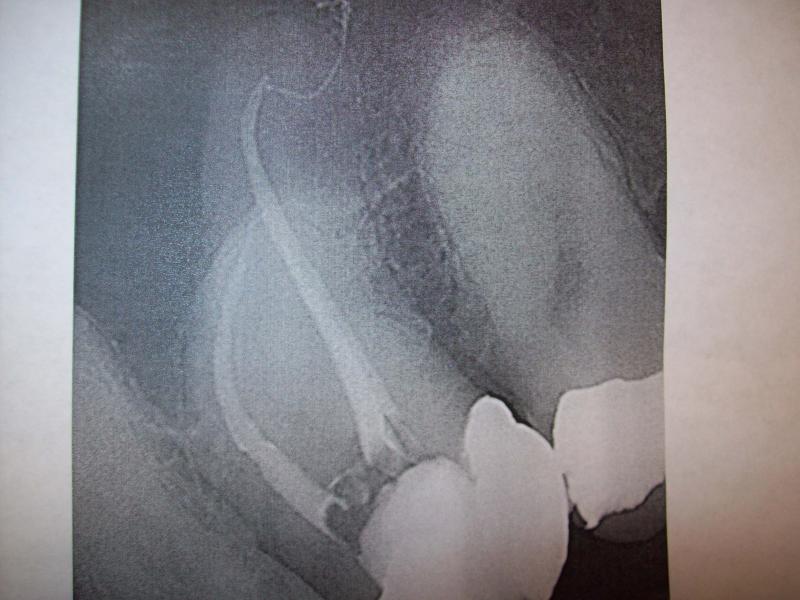

DR JET LOVES ROOT CANALS

General Dentist, Performs Root Canals ONLY - Microscope Trained Dentist

"DR. JET'S MISSION IS TO PERFORM ROOT CANALS FOR A REDUCED FEE USING THE LATEST TECHNOLOGY AND TECHNIQUES TO SERVICE THE MANY PEOPLE WHO ARE UNINSURED OR UNDER-INSURED GIVING EVERYONE AN OPPORTUNITY TO SAVE THEIR TOOTH!"